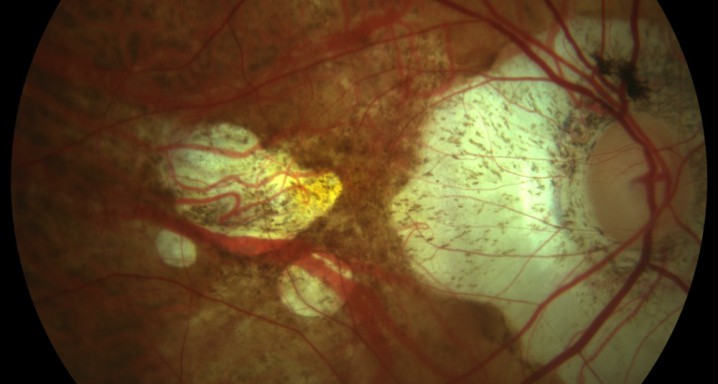

La miopía es un estado de crecimiento anormal del ojo, asociado a cambios degenerativos en su estructura. Se cree que la miopía patológica, en que la graduación sobrepasa las seis dioptrías, está causada por una alteración en el desarrollo del segmento posterior del ojo, y pueden aparecer diferentes complicaciones, como la atrofia coriorretiniana, la maculopatía miópica y el desprendimiento de retina.

Los pacientes con miopía tienen un elevado riesgo de presentar patologías retinianas, como por ejemplo enfermedades maculares o desprendimientos de retina, por lo que deben explorarse periódicamente para detectar posibles lesiones.

En caso de que se diagnostiquen complicaciones retinianas derivadas de la miopía, cada paciente recibirá un tratamiento personalizado, que puede requerir inyecciones intravítreas, fotocoagulación con láser o cirugía vitreorretiniana.

Tecnología e investigación: dos elementos fundamentales para la salud visual de nuestros pacientes. El Institut de la Màcula, en su afán por ofrecer a sus pacientes los mejores y más innovadores tratamientos, por la larga experiencia en el desarrollo y la utilización del protocolo Fusion para los casos de DMAE exudativa, dispone también de otros protocolos desarrollados para las membranas neovasculares secundarias a la miopía patológica que permiten frenar el daño causado por esta enfermedad.